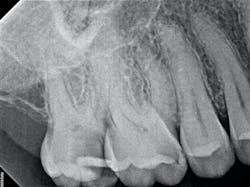

The iTero scanner was able to clearly define the delineation between the soft and hard tissue as can be seen in this image of the digital die trim (figure 3). Radiographs were captured on delivery revealing a clinically acceptable outcome for the patient (figure 4). Direct restorations were completed on teeth Nos. 3 and 4 during this visit.

By embracing digital technology, remarkable advancements in efficiency and clinical outcomes have been achieved. This case exemplifies the consistent and reliable results achievable through digital workflows, offering significant advantages over traditional methods.